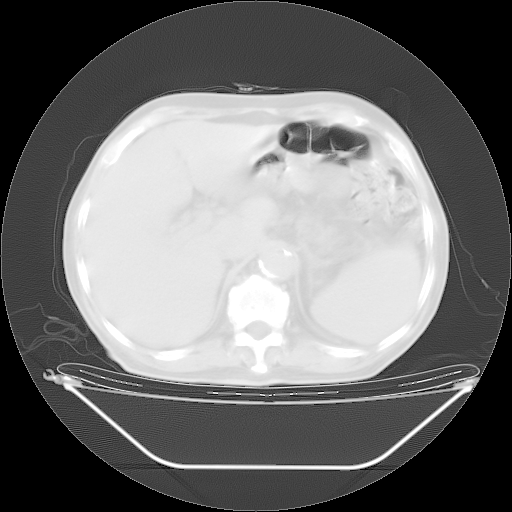

胸腹部CT,诊断意见:左上肺叶钙化灶、左侧胸膜局限性增厚并钙化、胆囊炎。描述部分肺组织呈磨玻璃样改变。

今天复查肺部CT,发现双肺广泛磨玻璃样改变。所以我把3月19日和5月9日相隔50天的肺部CT上传。请大家会诊。

2009年3月19日肺部CT片。

2009年3月19日肺部CT